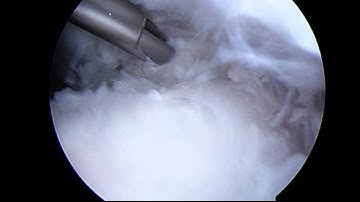

Arthroscopic Suprascapular Nerve Decompression